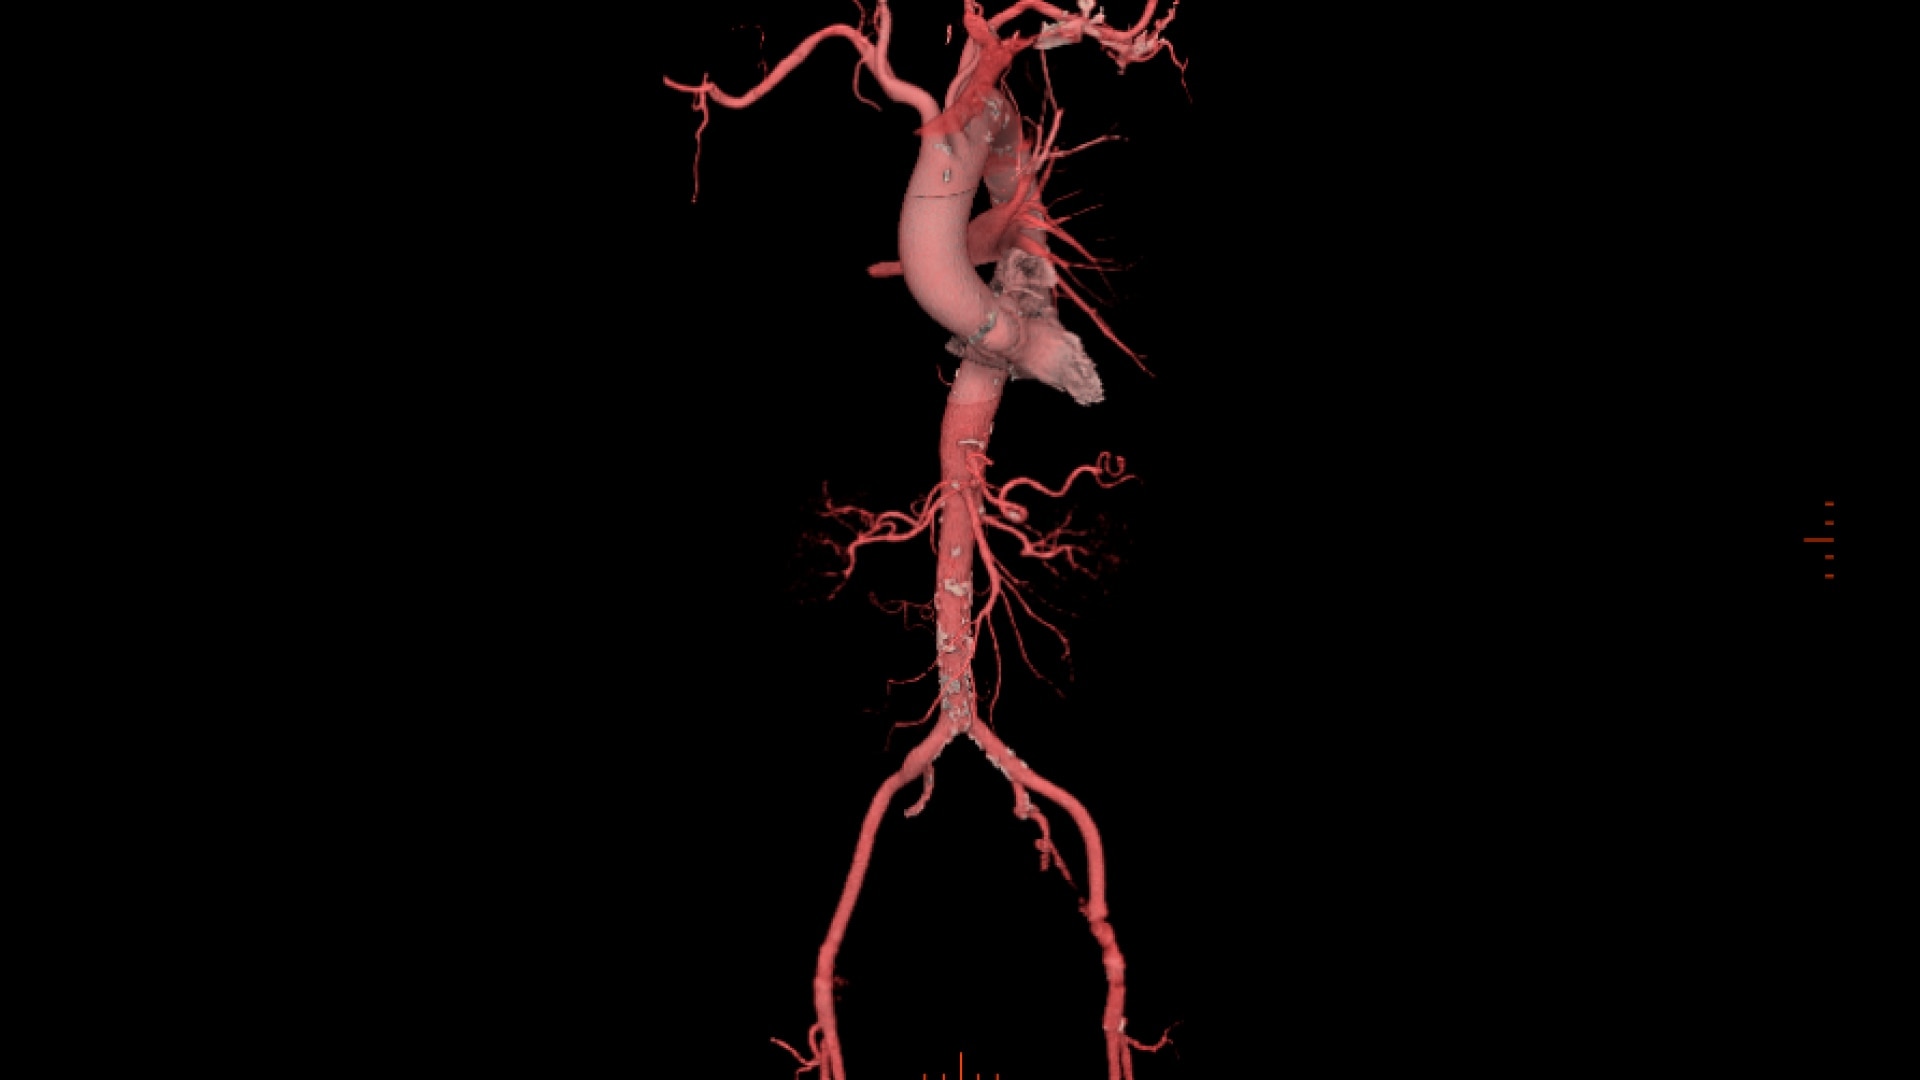

• Automatic centerline tracking for peripheral access planning

Assess aortic root and plan peripheral access within a single application